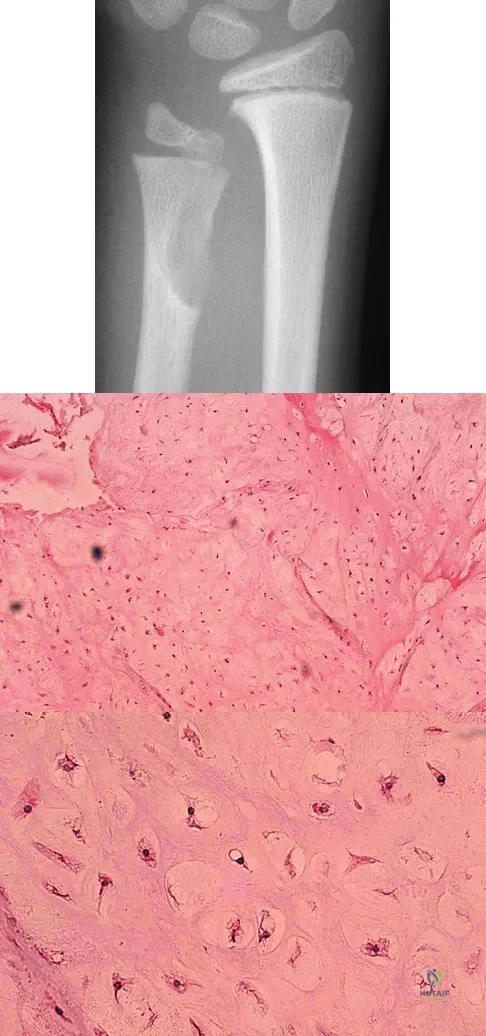

Question 74

A 10-year-old boy has had wrist pain for the past 3 months. He denies any history of trauma. He reports mild tenderness associated with a palpable mass. A radiograph and biopsy specimens are shown in Figures 52a through 52c. What is the most likely diagnosis?

Explanation